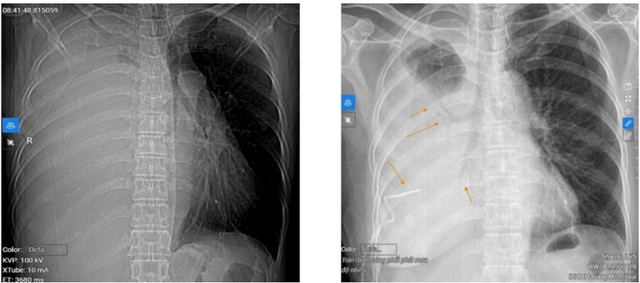

Kết quả chụp CT phổi cho thấy bệnh nhân bị tràn dịch màng phổi phải mức độ nhiều, gây xẹp hoàn toàn nhu mô phổi và đẩy tim, trung thất lệch sang trái. Ngoài ra, phát hiện một nốt đặc tại phổi trái kích thước 10x15mm, phân loại Lung-RADS 4X – nghi ngờ ác tính cao.

Hình ảnh trước khi dẫn lưu dịch màng phổi (ảnh trái) và sau khi dẫn lưu 1.000ml dịch màng phổi

Trước tình trạng nguy kịch, bệnh nhân được chỉ định thở oxy và chọc dẫn lưu dịch màng phổi cấp cứu dưới hướng dẫn siêu âm.

Sau 2 giờ, khoảng 1.000ml dịch màng phổi được dẫn lưu ra ngoài, giúp cải thiện rõ triệu chứng tức ngực và khó thở.